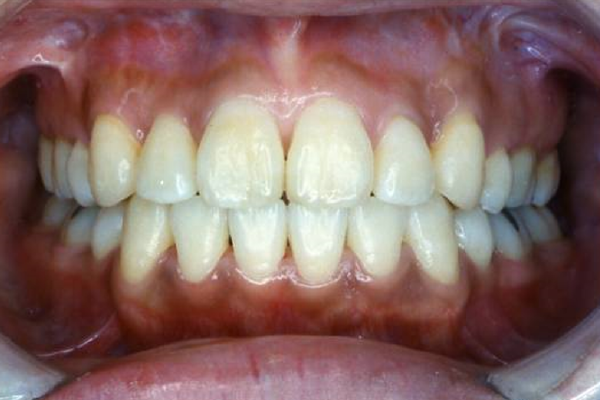

叢生改善後の笑顔

治療前は上唇が上がり、歯茎が多く見えていますが、治療後は上唇が丁度良い位置まで下がり、歯茎が見えなくなり歯の露出度が適度になっています。治療後の方が印象は断然良くなっており、患者様のコンプレックスが解消されたといえるでしょう。治療前には自信の無かった笑顔が、治療後には自信をもって笑顔になれるよう好転したのです。

①叢生(でこぼこ)の矯正治療例(30代女性・治療期間2年)

| 年齢・性別 | 30代女性 |

| 治療期間 | 2年 |

| 抜歯 | 上2本、下2本(小臼歯) |

| 治療費 | 50万円(調整費、保定費まで含む総額制) |

| 備考 | インビザライン |

| リスク・副作用 | 痛み・治療後の後戻り・歯根吸収・歯髄壊死・歯肉退縮 |